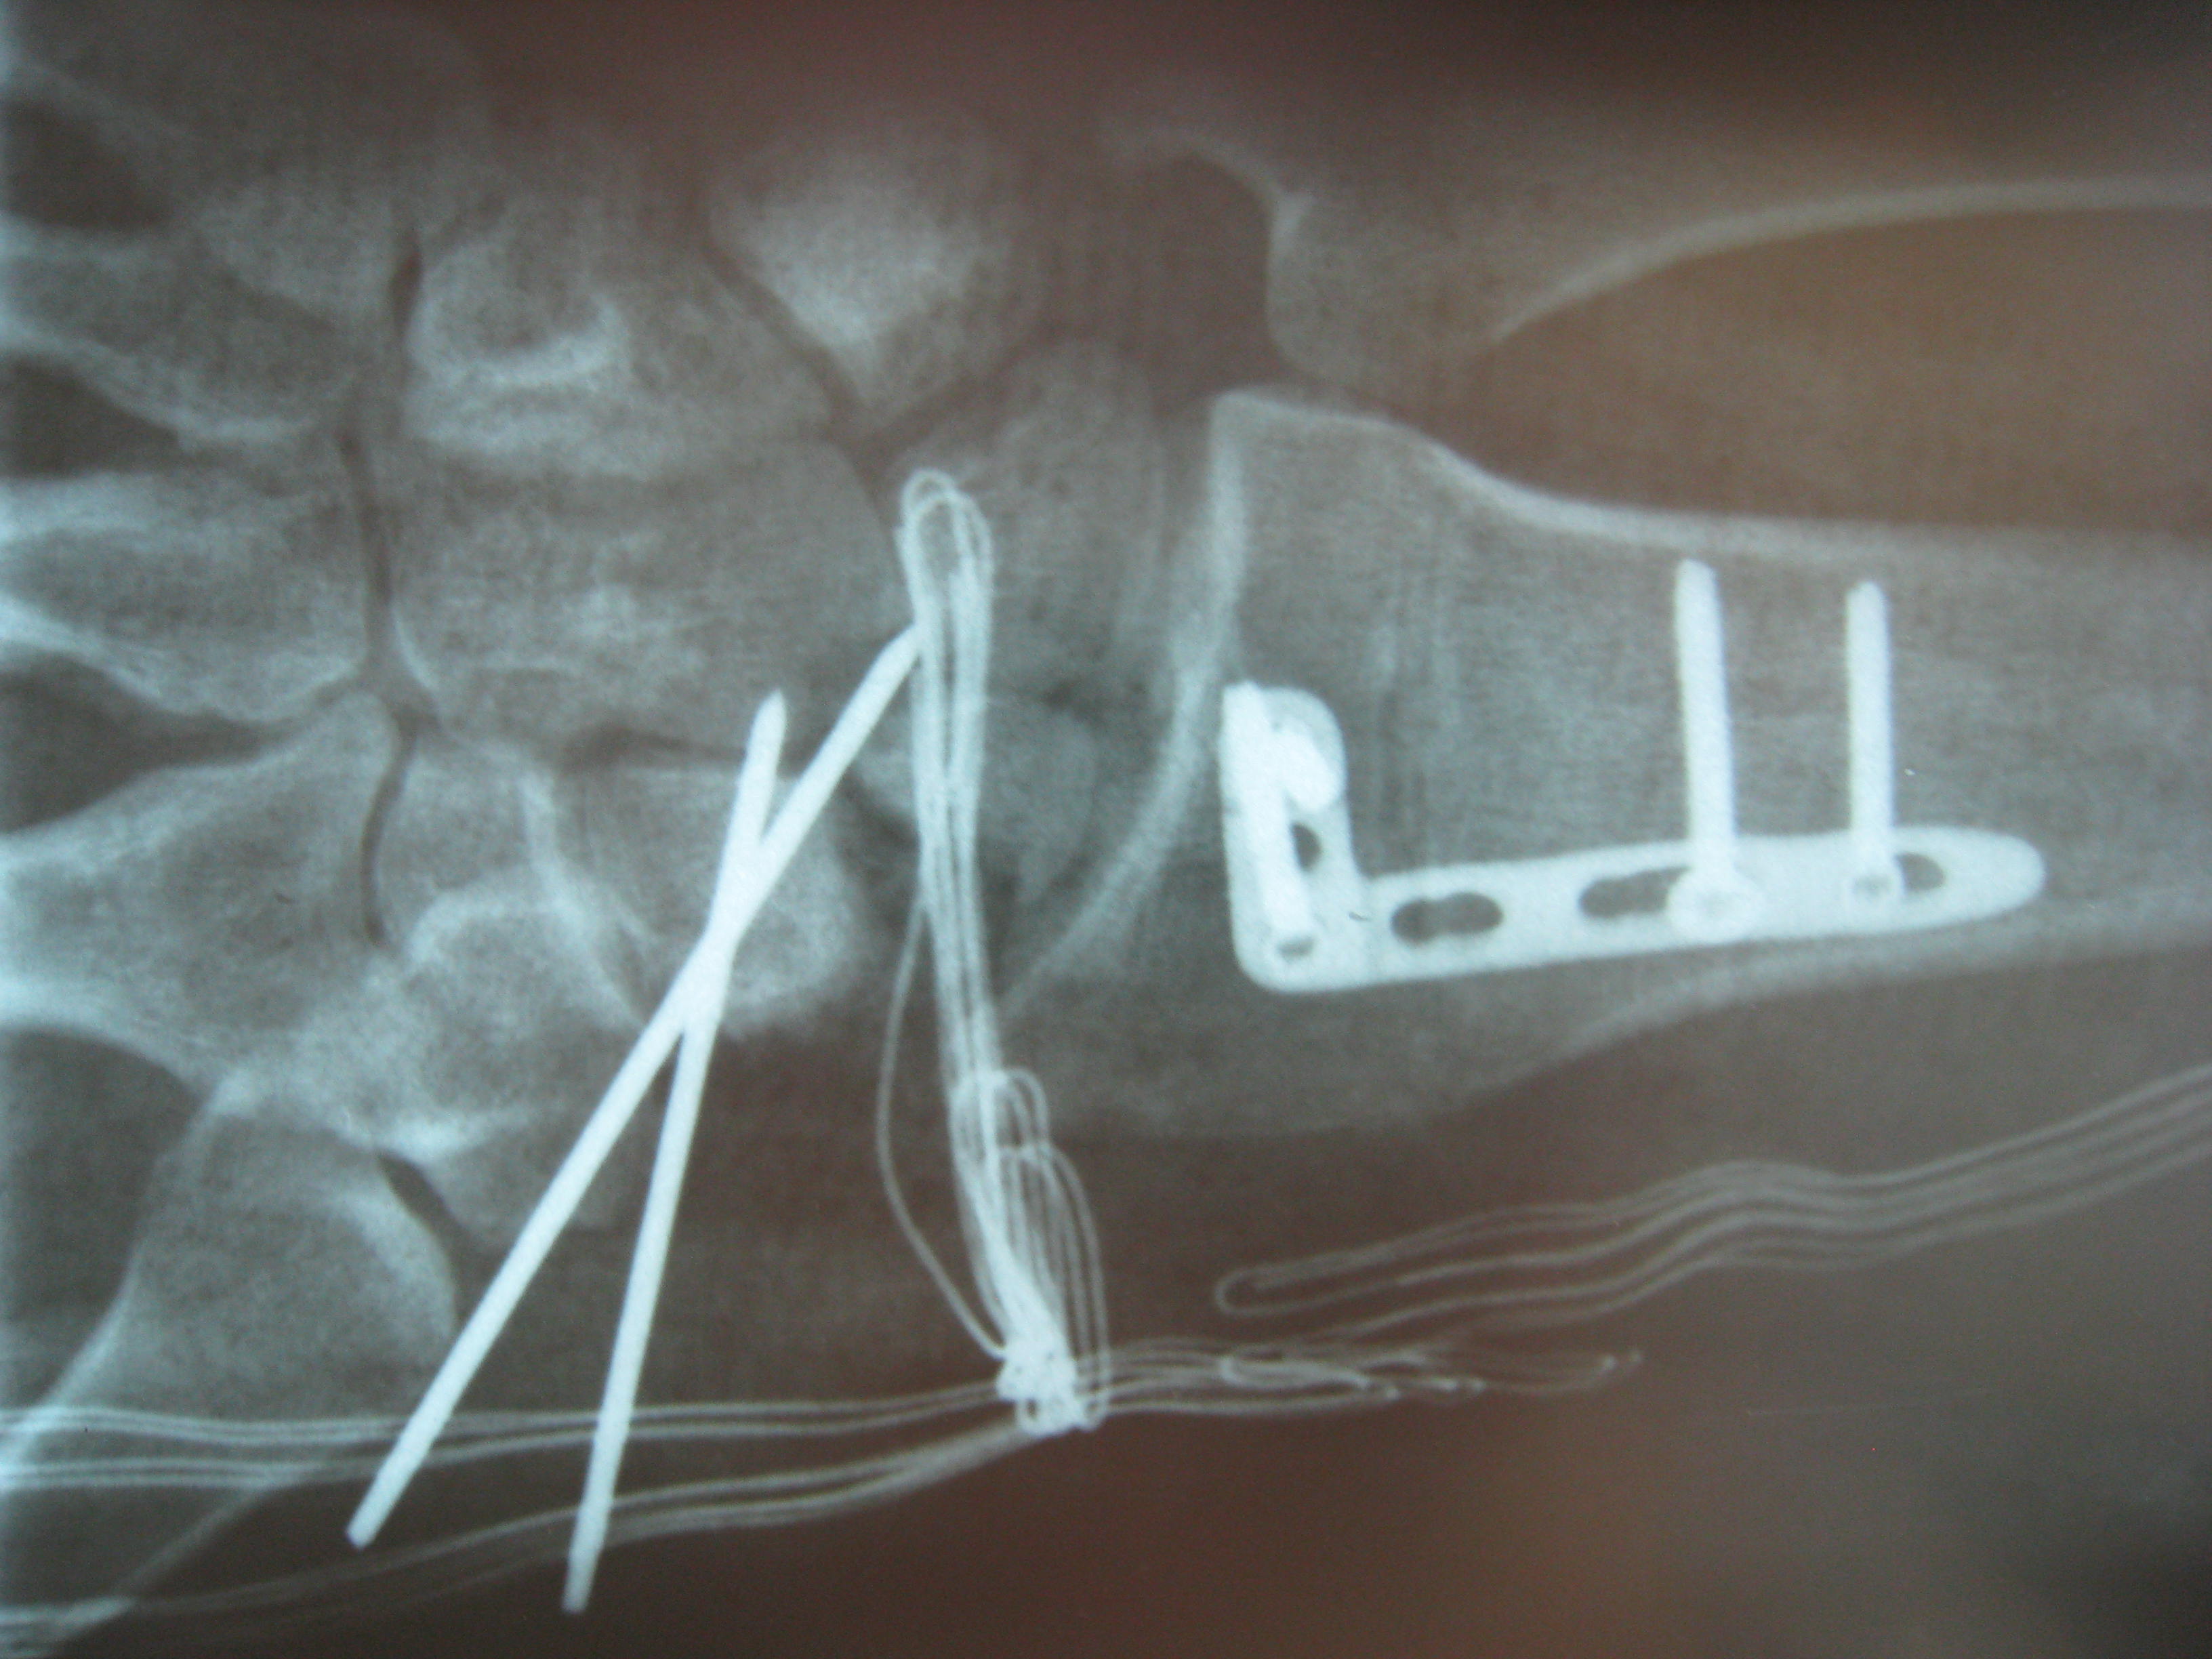

Περίπτωση 2: Μετεγχειρητικά 1

Η αντιμετώπιση της ψευδάρθρωσης του σκαφοειδούς είναι πάντοτε χειρουργική. Με ραχιαία ή παλαμιαία προσπέλαση αποκαθίσταται ο άξονας του σκαφοειδούς και σταθεροποιείται το σκαφοειδές με ειδική βίδα ή βελόνες, με παράλληλη τοποθέτηση οστικών μοσχευμάτων. Μπορεί επιπλέον να γίνει και οστεοτομία κλειστής σφήνας του περιφερικού άκρου της κερκίδος. Στις περιπτώσεις άσηπτης νέκρωσης το μόσχευμα πρέπει να είναι αγγειούμενο – για να προσδώσει αιμάτωση στο νεκρωμένο κεντρικό τμήμα – και λαμβάνεται με μικροχειρουργικές τεχνικές από το περιφερικό τμήμα της κερκίδος ή από άλλα τμήματα του σώματος